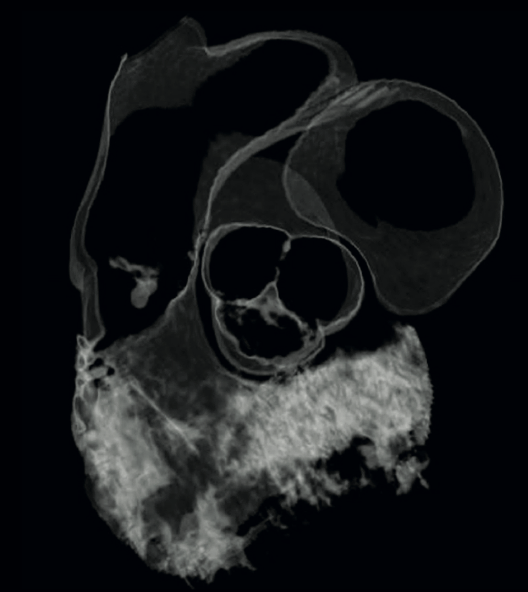

🫀✨ Cover-worthy cardiology ✨🫀 🍬This wasn’t just eye candy—it was last year’s journal cover. A stunning fusion of anatomy, pathology, and advanced cardiac imaging, submitted by one of our own cardiologists, Alex Rodriguez MD FACC! When clinical insight meets next-level

0

1

6

Just a reminder that cardiac imaging can be both 🧠 clinically brilliant 🎨 visually unreal This image was one of the @journalCCT covers last year—submitted by one of our cardiologists, Alex Rodriguez MD FACC🫀📸 #Radtwitter #Cardiology #Radiology #Radres

2

8